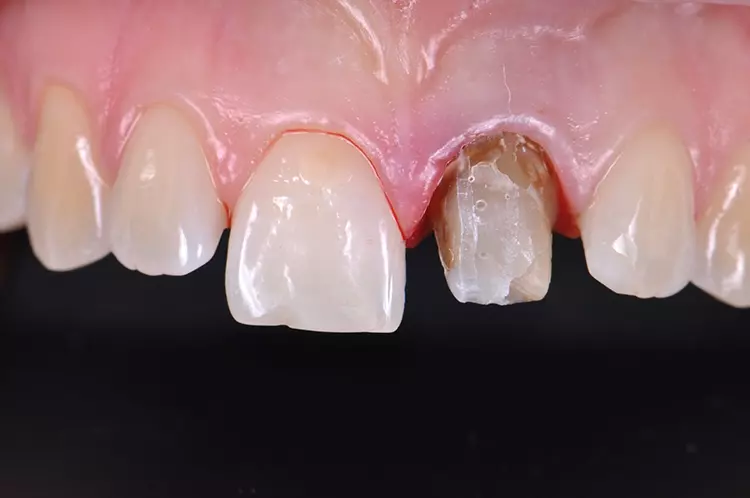

Im Rahmen des Erstgespräches berichtete die junge Patientin von einem Sturzereignis, bei dem der Schneidezahn frakturierte. Ihr damaliger Zahnarzt führte eine Wurzelkanalbehandlung durch und versorgte den Zahn mit einer Krone aus Lithiumdisilikat. Das anfänglich sehr ansprechende ästhetische Behandlungsergebnis hätte sich jedoch nach der Eingliederung mit der Zeit verändert und die Patientin stellte eine zunehmende Verfärbung der Frontzahnkrone fest (Abb. 2 und 3).

Dies kann aus einer nachträglich eingetretenen Verfärbung des devitalen Zahnes resultieren. Durch die sehr hohe Transluzenz der Glasphase einer Lithiumdisilikat-Restauration kann die dunkle Stumpffarbe durchschlagen und zu einem ästhetisch störenden „Grauschleier“ führen. In einem intensiven Beratungs- und Aufklärungsgespräch wurden der Patientin die Schwierigkeiten und Herausforderungen einer Einzelzahnkrone in der ästhetischen Zone bei einer hohen Lachlinie mit Exposition der Gingiva dargestellt.

Manche Details wie die Verfärbung der Gingiva wären nicht korrigierbar und verringerten die Vorhersagbarkeit eines optimalen ästhetischen Resultates. Die Neuversorgung dient der Verbesserung der ästhetischen Situation, eine perfekte Kopie des Zahnes 11 wird nicht zu erzielen sein, da die verfärbte Wurzel bestehen bleibe.